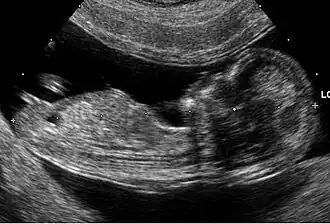

- Daarna verricht de arts zo nodig lichamelijk onderzoek en/of ander hulponderzoek (bijvoorbeeld bloedonderzoek, röntgenfoto's, echografie) en probeert al nadenkend, pratend en onderzoekend een of meer hypothesen op te stellen die de klachten kunnen verklaren, en die hypothesen te testen, meestal door te trachten ze te bevestigen (een heuristische strategie die voornamelijk op patroonherkenning is gebaseerd).[3][4]